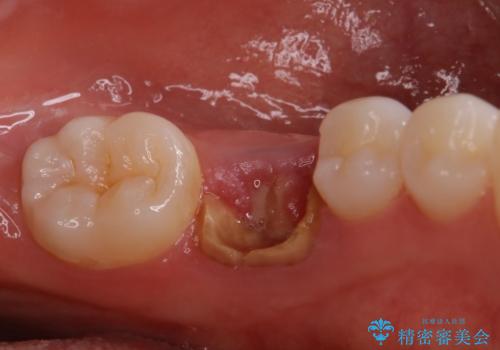

- 他院で抜歯と言われ、今後どうしたらいいのかを相談された患者様です。

抜歯を行った後は、Br、義歯、インプラント、何もしないという選択肢のメリットデメリットを説明させていただき患者様がインプラント治療を希望されたので今回治療させていただくことになりました。